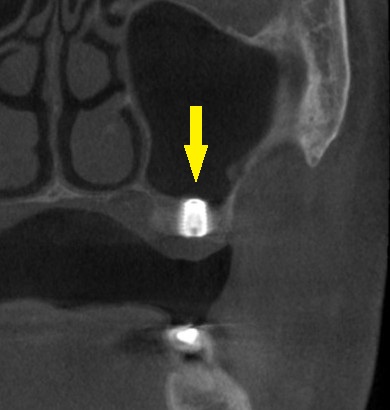

レントゲン、CTを撮影すると、骨幅は十分ですが、高さが3~4mmと、通常のインプラント埋入を行なうには、かなり不足でした。

本日、左第一大臼歯に直径6.0mm長さ7mm、第二大臼歯部位に直径5.0mm長さ7mm、のインプラント埋入術を施行しました。

下の写真が手術前後のCTです。